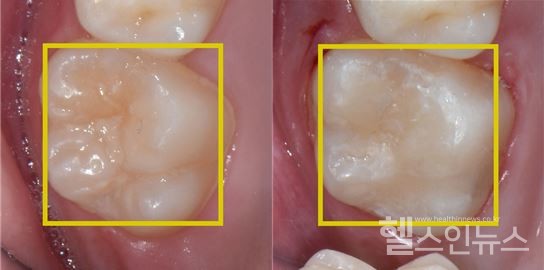

또 다른 항목은 흔히 레진 치료라고 불리는 ‘복합레진 치료’다. 만 12세 이하 어린이들의 영구치에 생긴 충치 치료를 지원되는 항목으로, 충치가 생긴 부위만을 정교하게 제거하고 특수 접착법을 시행한 후 치아 색과 유사한 복합레진이라는 재료를 이용해 원래의 치아 형태로 복원하는 치료다.

간혹 충치가 많이 진행되면 신경 치료(치수 치료)까지 필요한 경우가 있는데, 치수 치료가 필요치 않은 영구치의 경우에만 복합레진의 국민건강보험 적용이 가능하다. 또, 만 12세 이하 어린이의 영구치 복합레진 치료 시 국민건강보험 지원은 하루에 최대 4개까지만 가능하다. 만약 치료해야 할 충치가 4개가 넘는다면, 치료 후 다른 날 병원에 내원해 나머지 충치 치료를 받음으로써, 4개의 범위 안에서 다시 적용받을 수 있다.